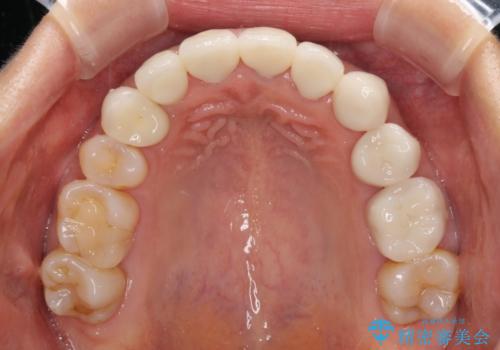

歯肉の高さをそろえたい 前歯の審美歯科治療

- 前歯の歯肉の高さが左右で異なっていることを気にして来院された患者様です。

歯肉レベルを調整するために歯周外科処置をおこない、その後にオールセラミッククラウンにて補綴することとしました。

処置後の痛みはあまり気にならず、歯肉位置の左右差もほとんどなくなり、患者様には大変満足していただきました。